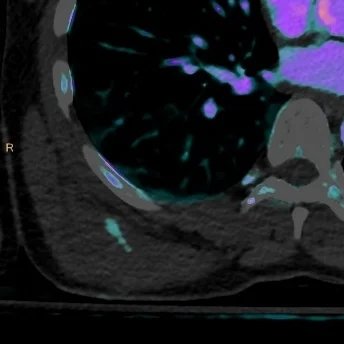

Low-contrast dose CT PE

Gopal Punjabi

March 15, 2018